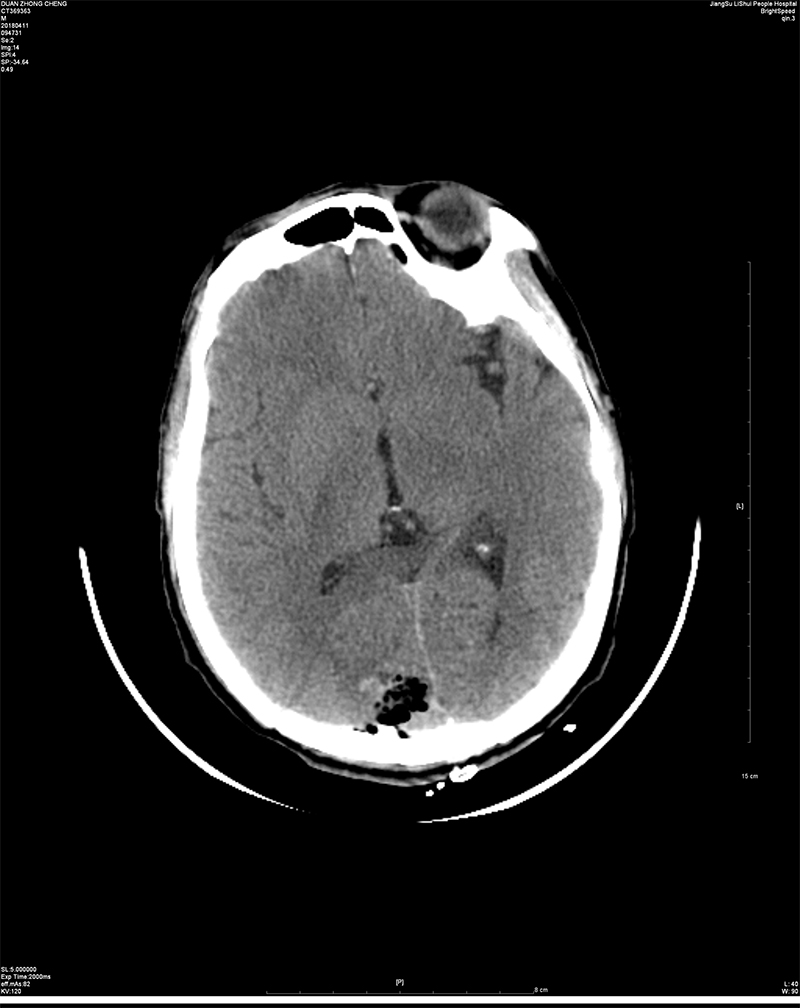

近日,我院神经外科成功完成一例矢状窦旁脑膜瘤切除术。 患者段某,男,64岁,已婚,南京溧水人。因“头晕一周,体检发现颅内占位一小时”入院。入院后经进一步完善检查,术前诊断考虑右侧顶枕部矢状窦旁占位:脑膜瘤可能。矢状窦旁脑膜瘤是肿瘤基底附着在上矢状窦并充满窦角的脑膜瘤。上矢状窦是大脑半球最重要的引流血管,不仅引流大脑半球皮质特别是中央前、后回等重要功能区的静脉血,而且也是脑脊液回流的最主要通道。该部位肿瘤因与上矢状窦及与很多汇入上矢状窦的大脑表面引流静脉关系密切,手术难度大,稍有不慎即可引起血管损伤破裂出血,甚至导致患者死亡等情况的发生,使得很多神经外科医师望而生畏。患者入院后,院长助理、神经外科赵鹏来主任带领全科人员仔细阅片、制定手术方案,科副主任杨平来主任医师、周立田副主任医师精心手术,最终顺利切除肿瘤。上矢状窦及引流静脉保留完好,无并发症发生,目前患者已康复出院。 近年来,神经外科在院领导及科主任的带领下,积极响应区里及院里的号召,刻苦钻研,努力提高医疗技术及服务水平,争创南京市医学重点专科,积极投入到创建三级医院的工作中,以满足我区人民日益增长的就医需求。目前,神经外科不仅能够开展常见的各类脑外伤、脑出血、脑肿瘤、脑积水等手术,同时已具备开展颈动脉内膜剥脱(CEA)及动脉瘤夹闭等特殊类型手术的条件和能力。神经外科将一如既往钻研新技术,以方便患者在家门口就医,提高社会满意度。

术后复查CT